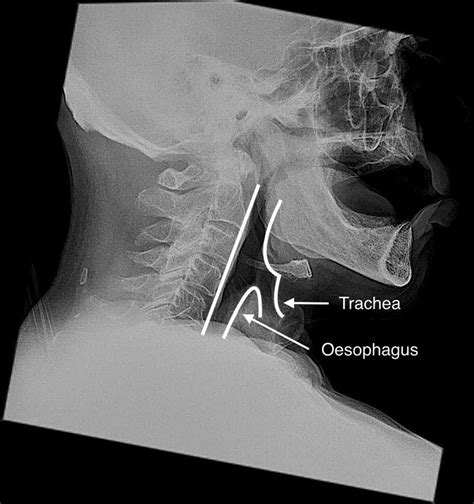

A Soft Tissue Neck Xray is a medical imaging technique that uses low-dose X-rays to produce images of the soft tissues in the neck region. Unlike traditional X-rays that focus on bones, a soft tissue X-ray is designed to visualize structures such as muscles, tendons, and ligaments. This makes it an invaluable tool for diagnosing conditions that do not involve bone abnormalities.

• Foreign Bodies: To locate and identify foreign objects that may have been ingested or lodged in the neck.

• Foreign bodies

• Foreign Bodies: Objects that may have been ingested or lodged in the neck.

• soft tissue neck anatomy xray